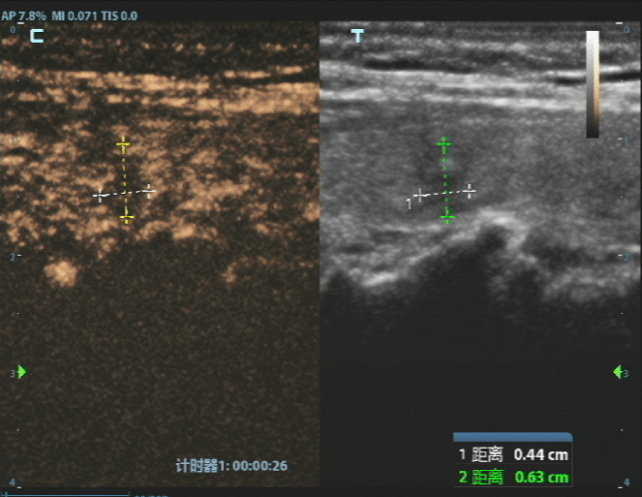

消融前病灶

经过严谨评估,刘女士首先接受了甲状腺穿刺活检。病理结果证实了最坏的猜想——甲状腺乳头状癌。但紧随其后的详细评估,却带来了好消息,结节微小、单发、未转移、未侵犯包膜,完全符合射频消融治疗的黄金指征。

这个方案瞬间让刘女士放下了所有的担忧。随后,白国栋主任团队便为她实施了超声引导下甲状腺结节射频消融术,整个过程仅十几分钟。治疗结束时,刘女士几乎不敢相信地说,“就这么好了?我根本没有任何不舒服的感觉。”

消融后病灶